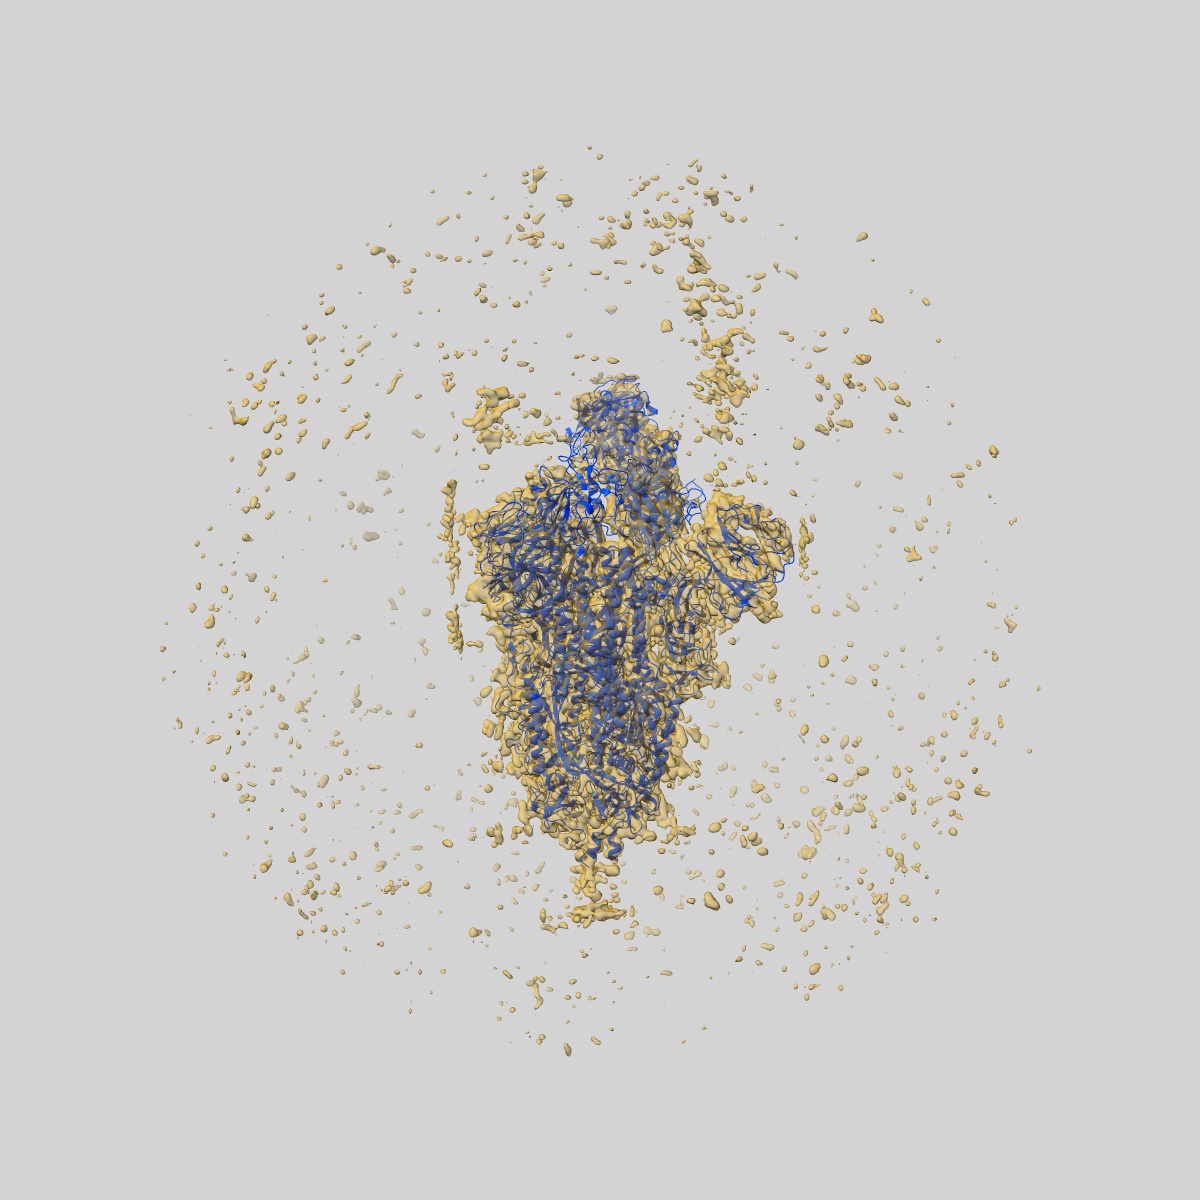

EMD-32683

SARS-CoV-2 Omicron Variant S Trimer complexed with one JMB2002 Fab

Single-particle3.18 Å

Sample: SARS-CoV-2 Omicron Variant S Trimer complexed with JMB2002 Fab

Fitted models: 7wpd

Structures of the Omicron spike trimer with ACE2 and an anti-Omicron antibody.